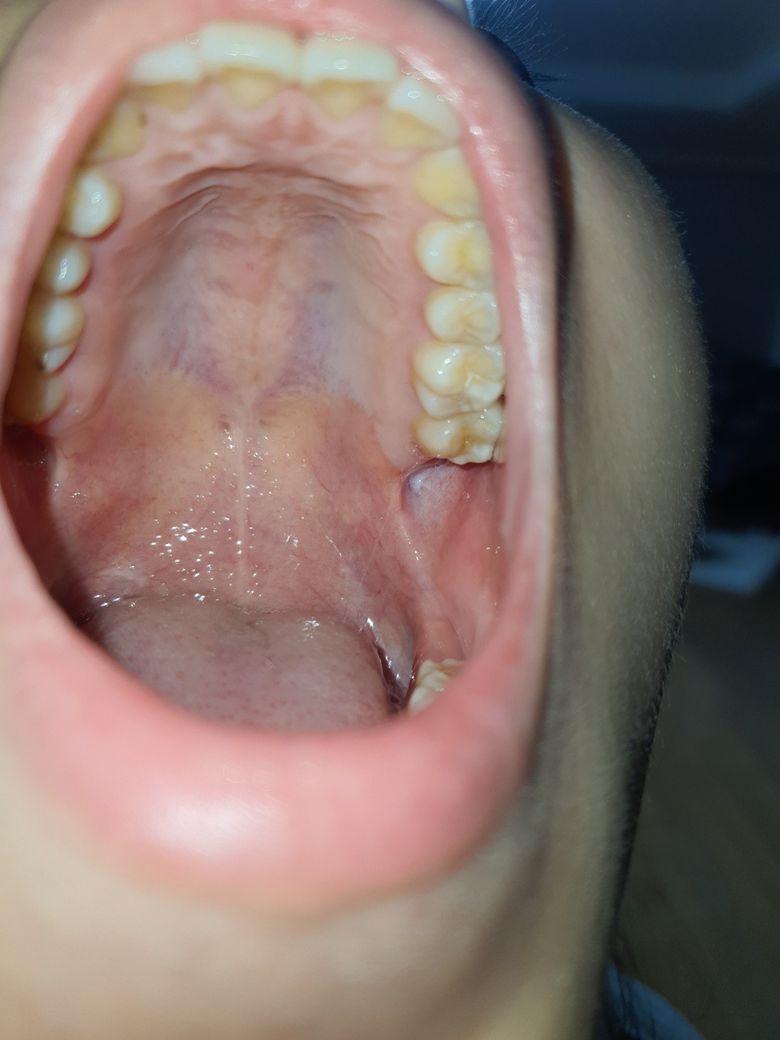

상악사랑니 발치 경과 한번만 봐주세요!

한달 조금 넘었는데 아직 혀로 건드려보면 달랑달랑거리고

말랑말랑해서 사진 찍어서 보니까 이렇게 하얗더라구요.정상인지 한번만 봐주세요!

사랑니 발치후 한달정도면 잇몸은 잘 아물어있는 듯 합니다. 조직이 덜렁거리면 제거가 필요할 순 있습니다.

치유가 매우 잘 되었으니 전혀 걱정하지 않으셔도 되겠습니다 안에있는 뼈가 다 차려면 3-4개월정도는 걸립니다.

발치부위 염증 소견입니다 해당 부위 위생관리를 잘해주시기 바랍니다 염증은 자연히 사라질 것 같습니다

사랑니 발치한곳이 아직 다 아물지 않아서 그러는거 같습니다. 시간이 조금더 지나면 괜찮아 질꺼니 너무 걱정하지마세요.

통증이나 붓기가 없는 경우에는 문제가 되는 상태는 아니며, 현재 사진상에도 잘 아문것으로 보입니다. 만약 통증, 붓기, 악취, 고름이 나오는 경우에는 염증의 가능성이 높기에 치과 진료를 권합니다.

사진으로 봤을 경우에는 크게 문제가 없이 잘 아물고 있는것으로 보입니다. 해당부위가 자극이 되지 않도록 하는것이 치유에 도움이 됩니다.